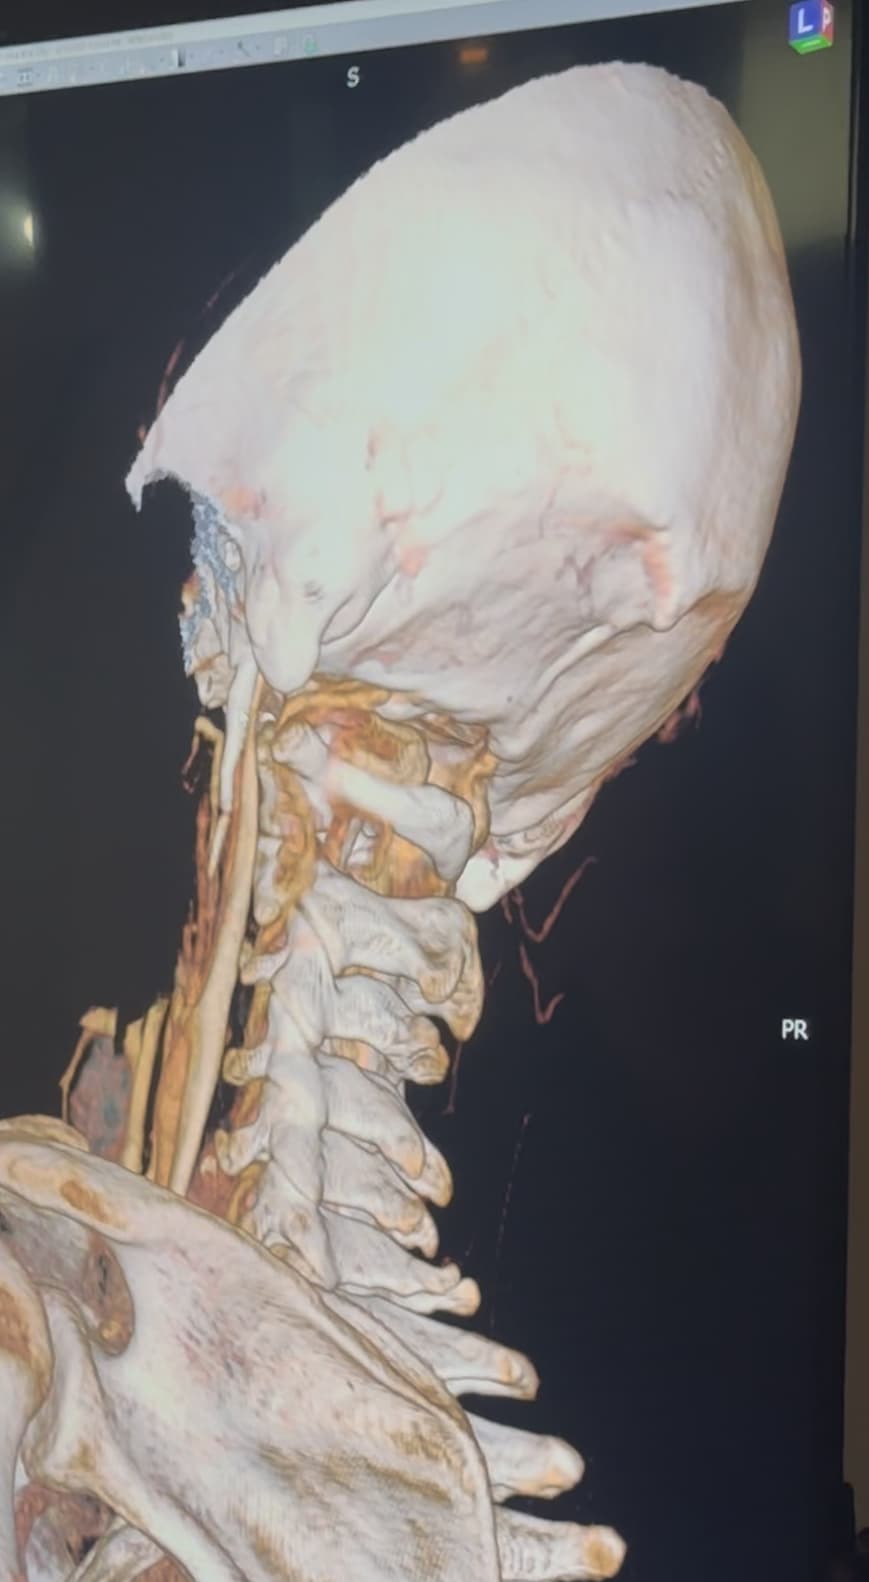

Hi Rob & welcome! Looking at your CT, & obviously we’re not experts, I would estimate that your styloid & calcified ligament section is longer than 5 cm; on your left in the middle image it goes way past your C2 vertebra! We have found that the measurements from CTs are often wrong as it can be quite hard to measure accurately due to CT imaging being done in slices…

The IJVs do collapse naturally when flat, so it could be due to that, in your 3rd image it looks like the IJV is flattened higher up, so what would be right by the skull base. It could be like that naturally because of being flat for the CT, or it could be that it is being compressed where it emerges from the skull at the jugular foramen - if styloids are quite thick that is possible, & yours do look a little wide at the top… It looks like there could be something pinching the IJV between it & the styloid where you’ve marked too; we’ve had members who’ve had compression from an enlarged SCM muscle, the digastric muscle, omahyoid muscle, as well as other blood vessels & nerves… I’d guess where the compression is that the digastric muscle would be the most likely if it was a muscle, or maybe the stylohyoid muscle, although we don’t hear much about that one!

@Rob12345 - Welcome to our forum! I have nothing to add to what @Jules said, but did want to say WOW! You do have very long styloids. The “kink” in your ICA (internal carotid) isn’t really a kink more of a curve, but I can see based on the image, that it could be causing some slowed or backed up blood flow going into your brain. The IJV compression is curious as it appears to be more than the styloid causing the problem but clearly C1 seems not to be involved. I think Jules has made some logical assumptions regarding other possible compression culprits.

@Rob12345 - I can see you have bilateral IJV compression in the images you’ve posted & it’s possible the middle image in your first set of pictures is pointing to collateral veins. I’m not great at identifying collaterals, but I can say for sure your IJVs are being squashed between your styloids & C1.